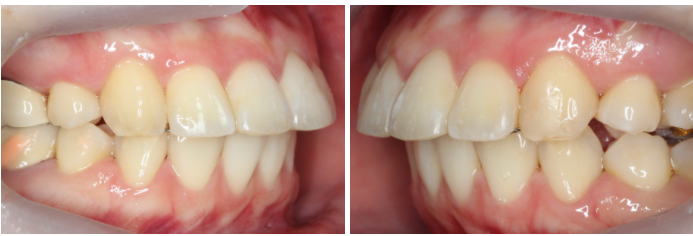

상악 클리피씨 교정 case

위의 case는 토끼앞니교정을

진행하기 전 정밀진단 상황으로

상악 중절치의 돌출감이

심한 모습인데요,

특히 upper teeth와

lower teeth의 정중선이

어긋나 있기 때문에

전치부의 crowding이

더 강조되는 상황입니다.

전치에서 구치까지 이어지는

협측 사진을 보시면 중절치의

튀어나온 모습을 명확하게

확인할 수 있습니다.